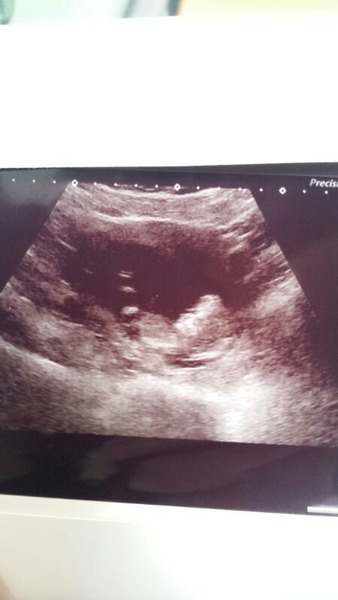

Hiya everyone and good luck for scans today just wanted to pop in and share my scan photo of little kitten haha. All seems well I didn't get to see much of the scan but got to see nice strong heart beat. Such a relief!

Leaving the first trimester behind and hopefully all the sickness and worry that has come with it. January 2015 thread #5

mummyk8 · 27/06/2014 11:04

littlecat123 Aw so so cute.

i couldn't resist joining in ... here is my little one. Not the clearest image (need to scan it in)

12+5 today